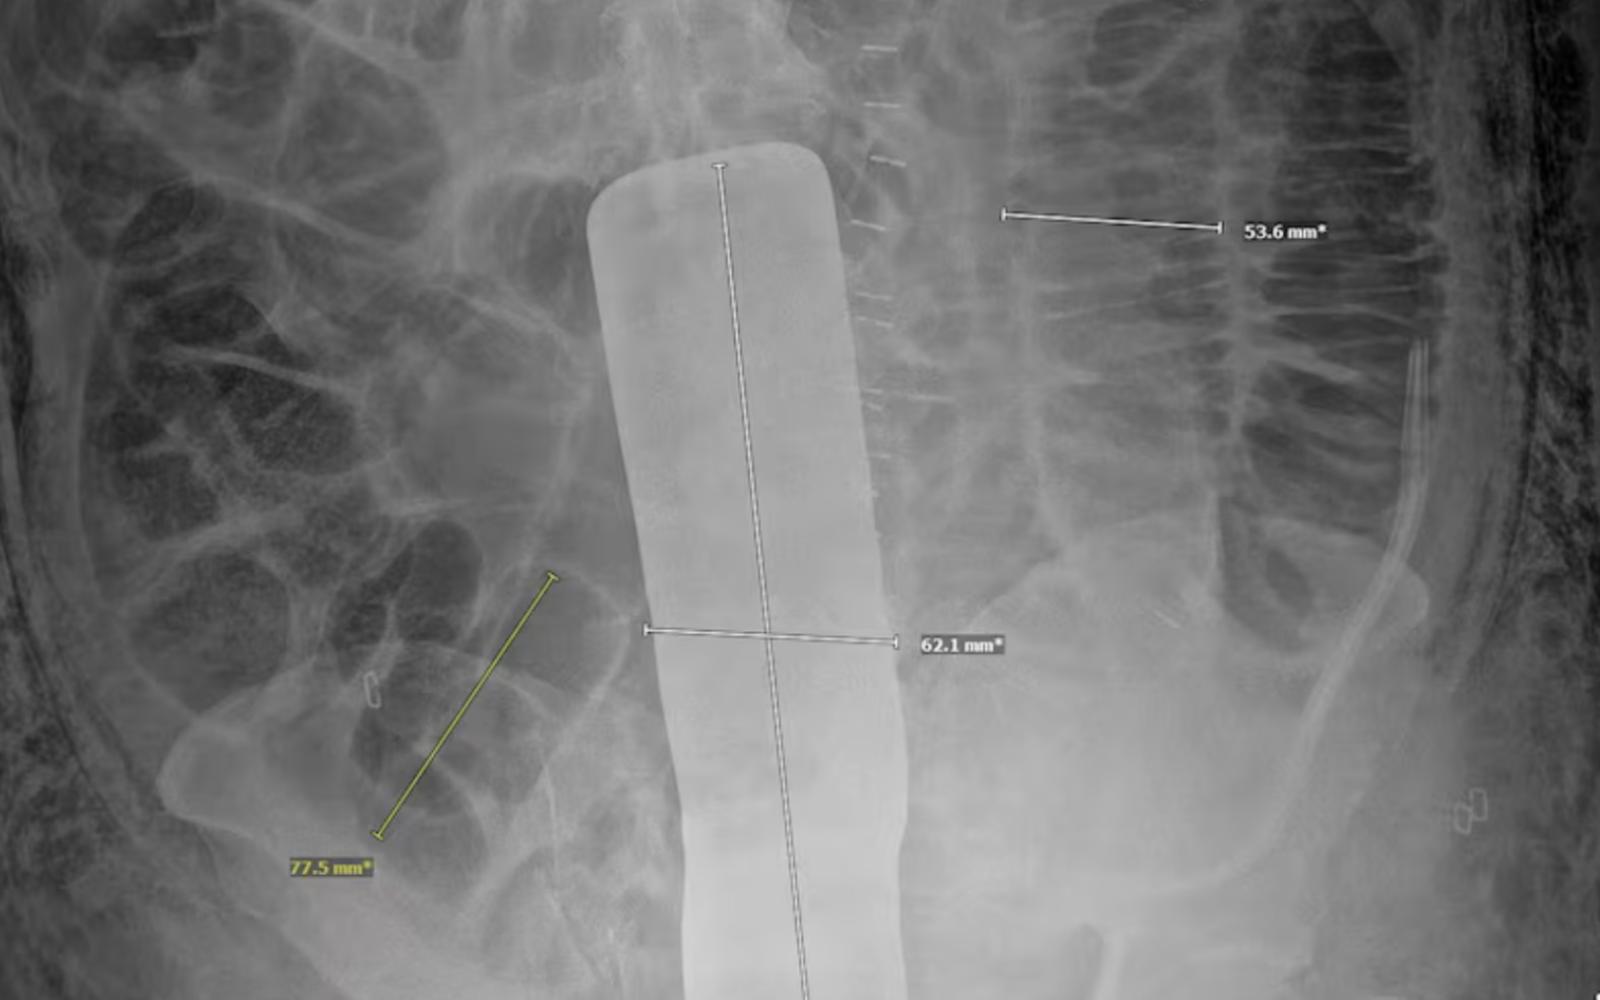

An X-ray ordered by his doctor revealed the instrument, which Nava’s attorney, Les Weisbrod, displayed during a Wednesday news conference. Four days after the tumor removal, Nava underwent a second operation to remove the tool.

X-Ray of the Surgical Tool sealed inside Genaro Nava

(Credit: Dallas Morning News)